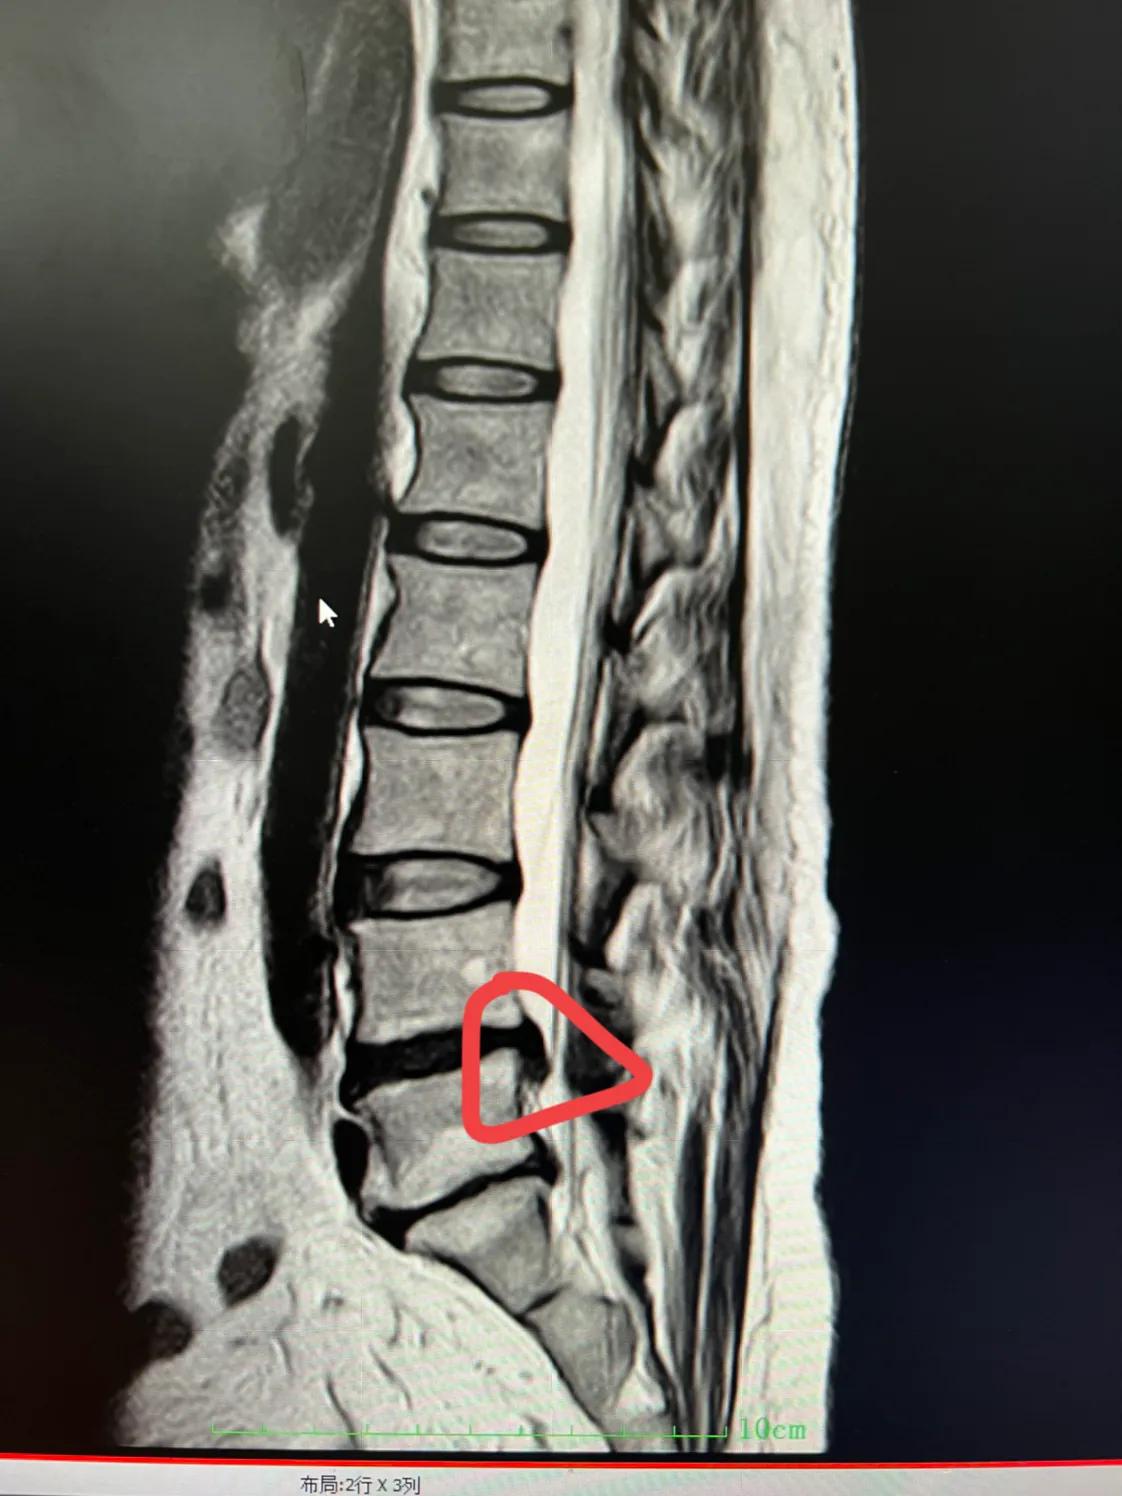

其实,椎间盘脱垂也是椎间盘突出的一种类型,一般的椎间盘突出,是基本平行于椎间盘的,但“脱垂”,却是突出后的椎间盘向下滑落了。

这种椎间盘突出,很难治疗,基本只能手术。